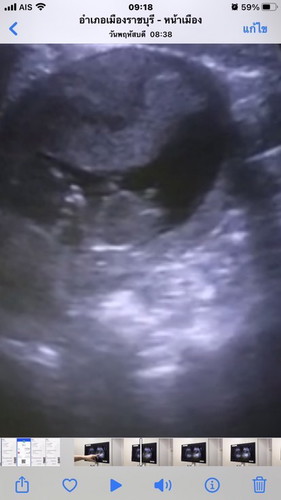

มีแม่ท่านไหนไม่แพ้ท้องบ้างคะ คือเราหยุดแพ้ตั้งแต่8wแล้ว ไม่แพ้เลย แต่ชอบนอน คืออยากนอนทั้งที่พึ่งจะนอนไปก็นอนหลับได้ ชอบกินพวกซีส ช็อกโกแลต มากกว่าปกติก่อนท้อง รบกวนช่วยดูภาพซาวนิดคะมีโอกาสได้ลูกชายมัยคะ